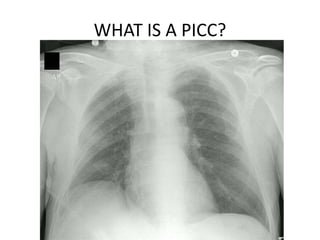

WHAT IS A PICC?

A peripherally Inserted Central Catheter (PICC)

is a long, thin, flexible tube that is used for

giving intravenous fluids and medications. It is

inserted through a peripheral vein, preferably

in the upper arm and advanced until the tip of

the catheter reaches a large vein above the

heart.